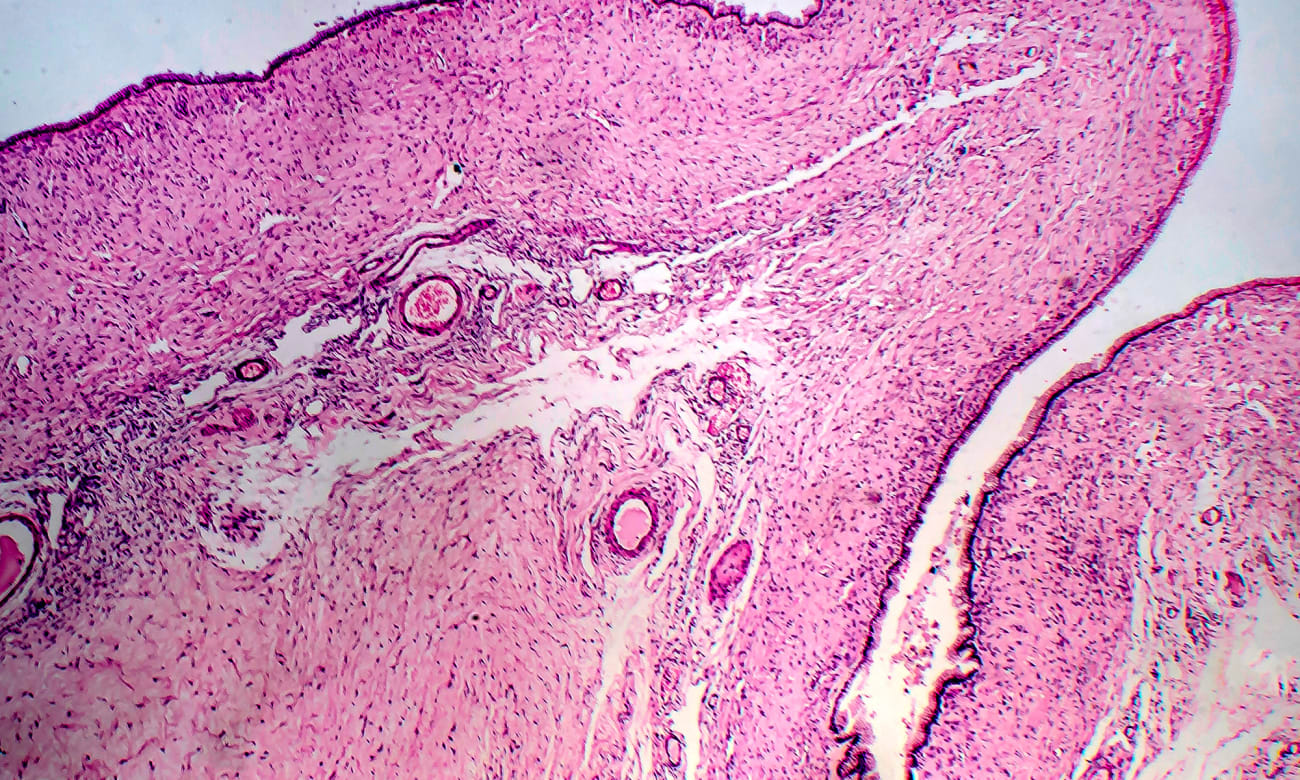

Minimally invasive surgeries form the foundation of gynecologic ERAS pathways, and this is an area in which Johns Hopkins excels, explains Johns Hopkins gynecological surgeon Karen Wang. She serves as director for Johns Hopkins’ AAGL-accredited fellowship in minimally invasive gynecologic surgery, one of the few training programs of its kind in the United States. Wang notes that Johns Hopkins is relatively unique in performing the vast majority of hysterectomies and myomectomies as outpatient procedures — as well as even more complicated cases, such as resecting large or multiple fibroids.